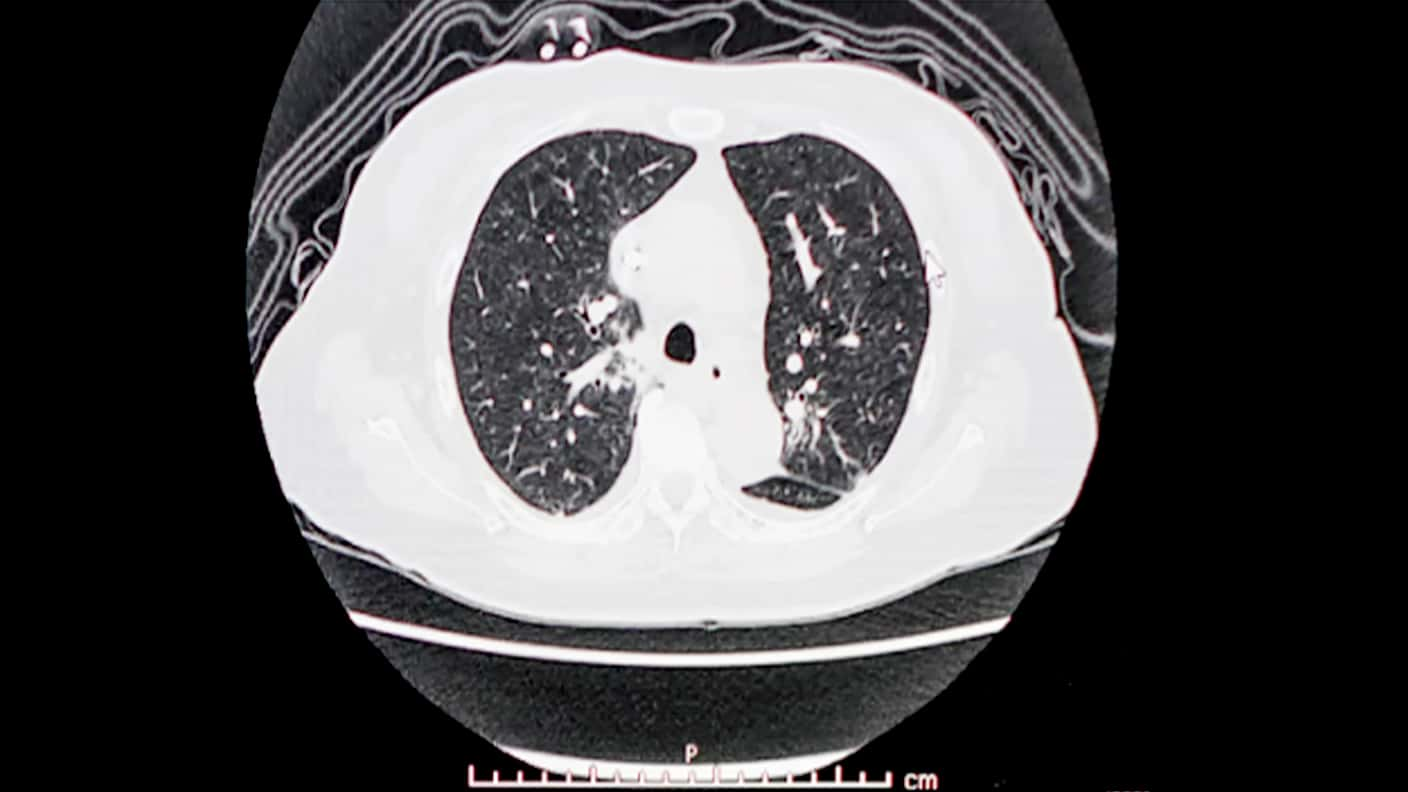

CT検査はX線を使って体の内部を撮影、レントゲンやエコーと違い、体を輪切りに撮影して小さな病変を発見します。X線検査 (レントゲン) で見つけにくいような小さな病変の早期発見にも有効と言われています。

※ 胸部CTか腹部CTどちらか1つを選択いただきます。

※ 画像はイメージです。

胸部CTでは、主に肺の疾患 (肺がん、肺炎、肺気腫) や、心臓・心血管の疾患・異常 (狭心症、心筋梗塞) を、腹部CTでは腹部臓器 (肝、胆、膵、脾、腎臓) の腫瘍などの病変の早期発見に有効です。

肺のCT画像